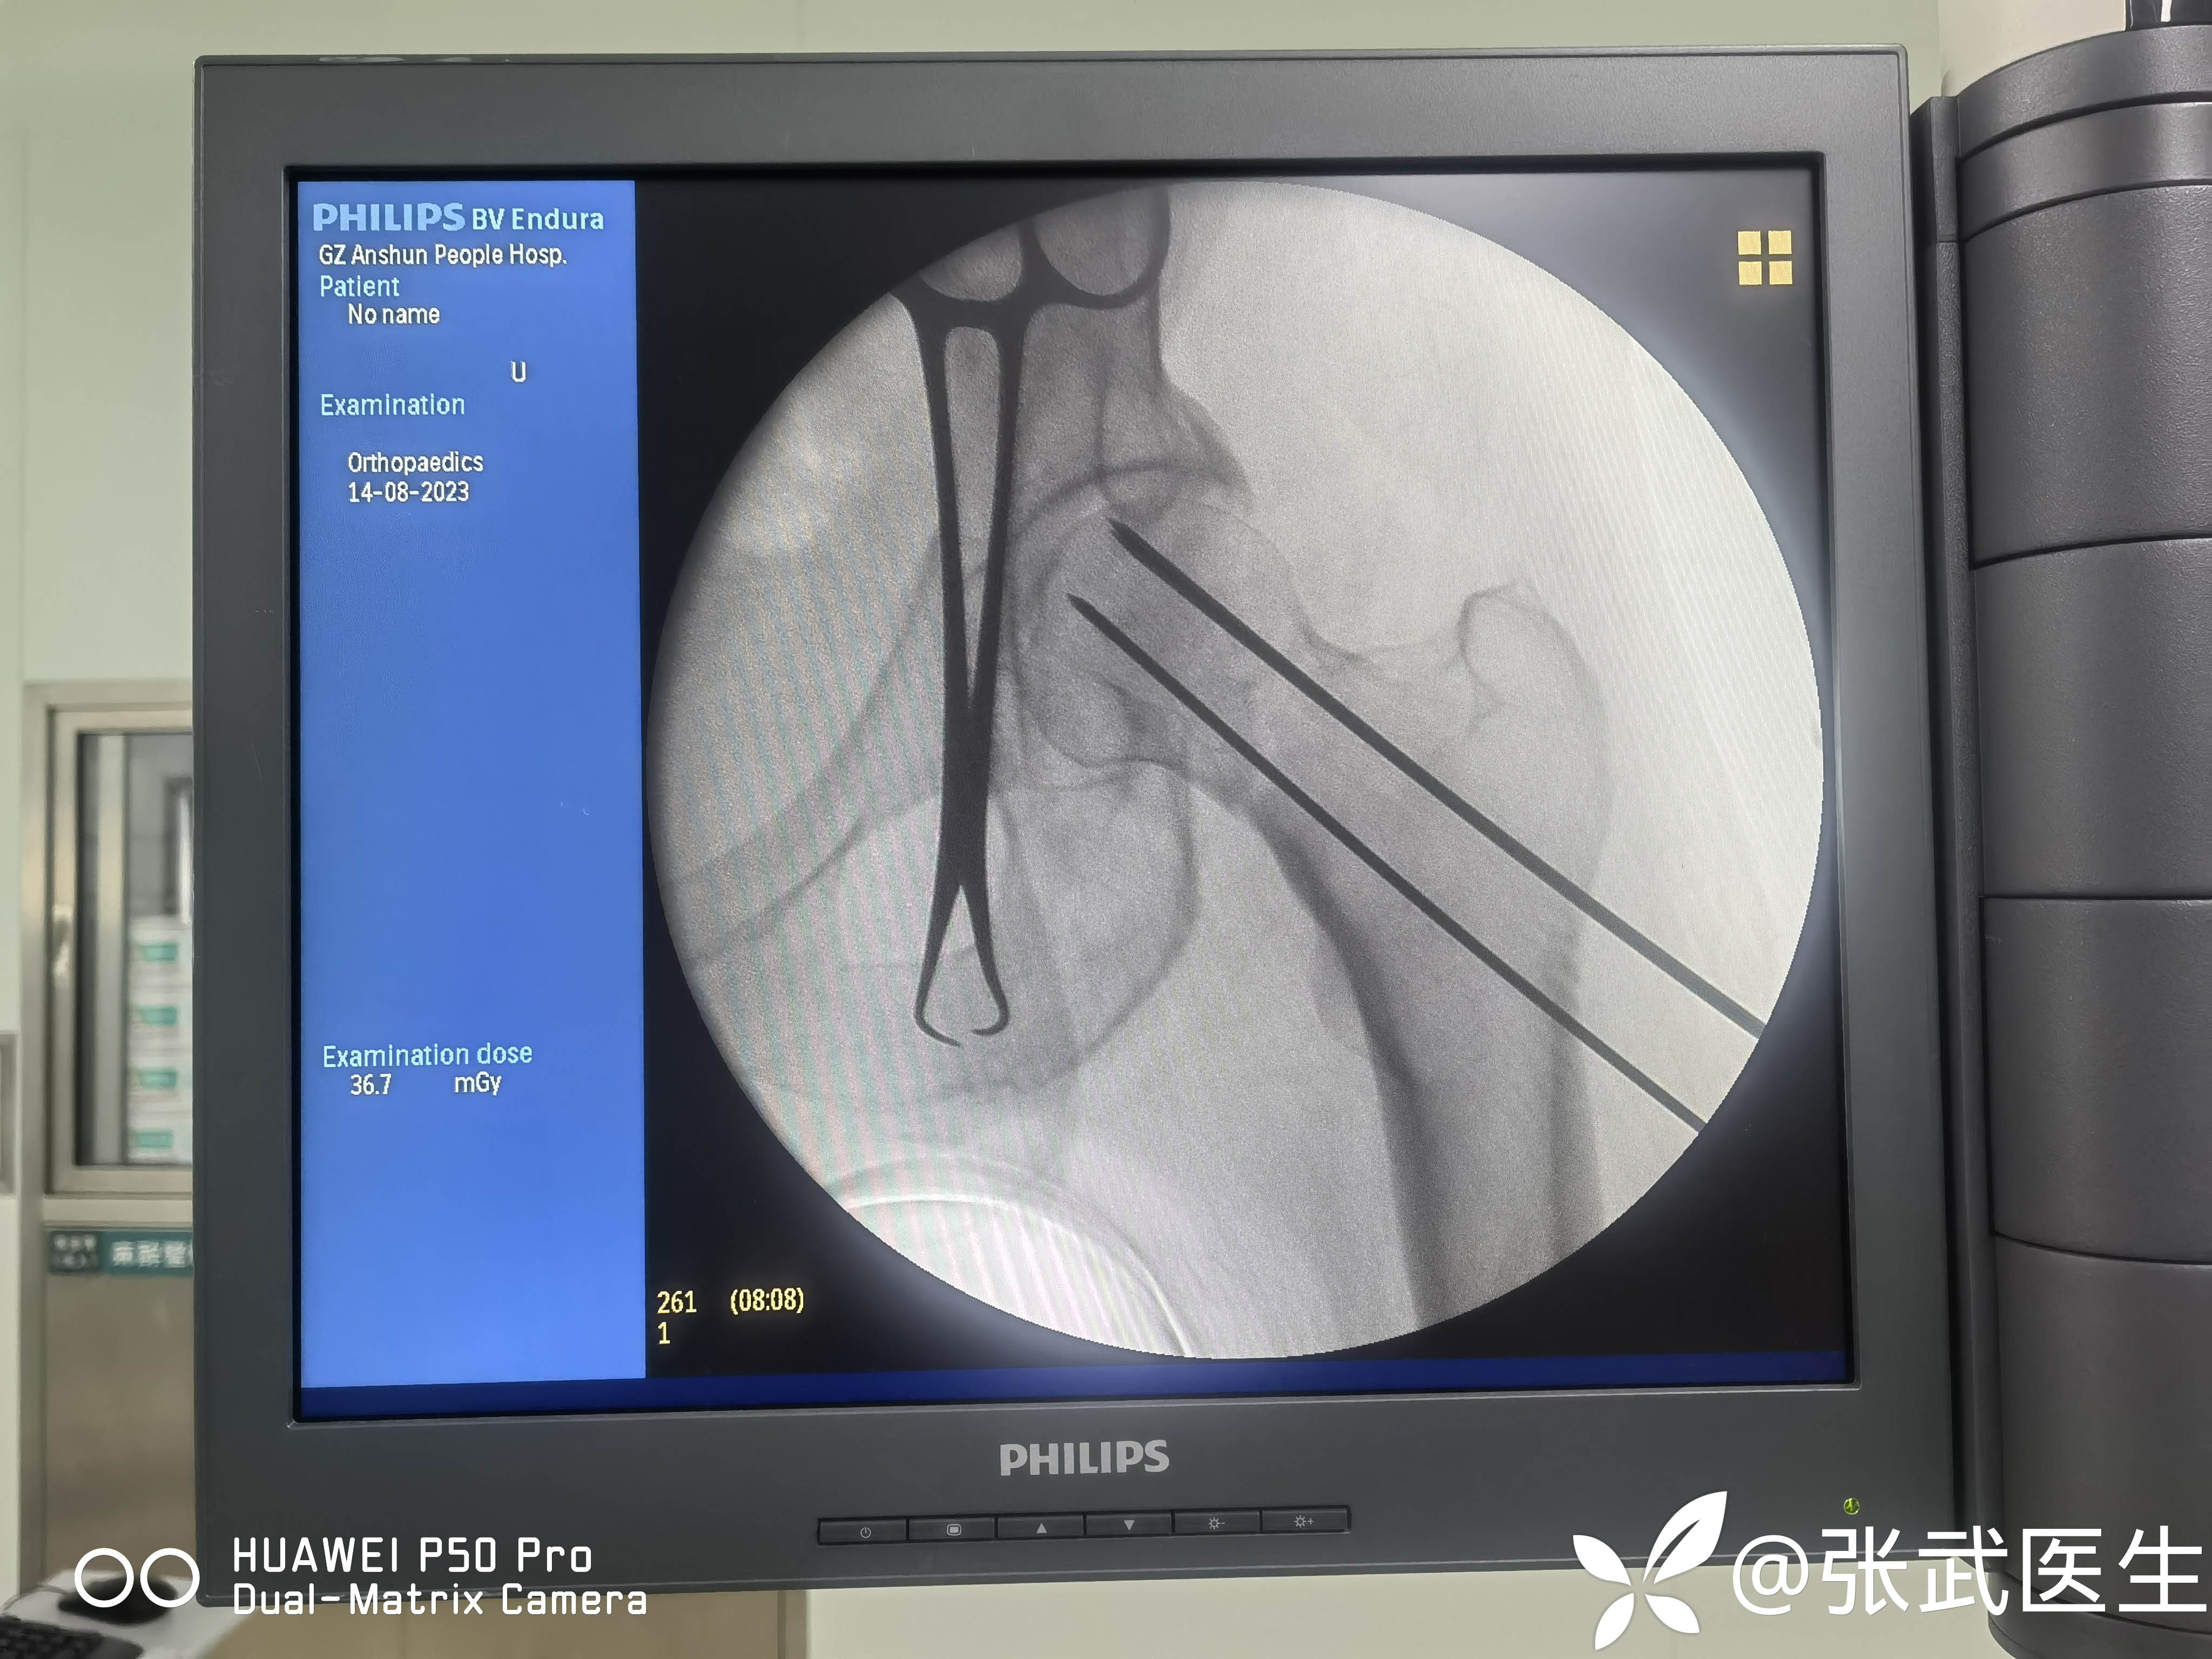

克氏针置入情况

先置入股骨距克氏针,以此为参照物置入另两枚,呈倒三角。